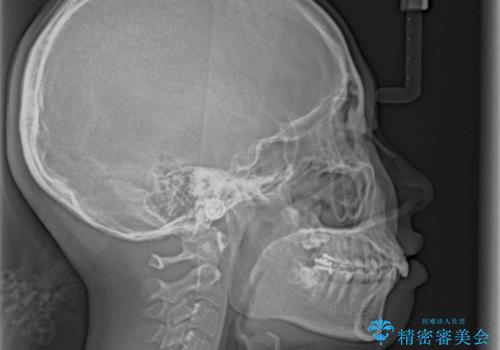

下顎骨の左右差や、上顎骨の前方位などが認められたため、上下左右の第1小臼歯4本を抜歯し、ワイヤー装置にて矯正治療を行うこととしました。

骨格的な左右差がありましたが、何とか当初予定していた期間で、左右対称の咬み合わせに仕上げることができました。